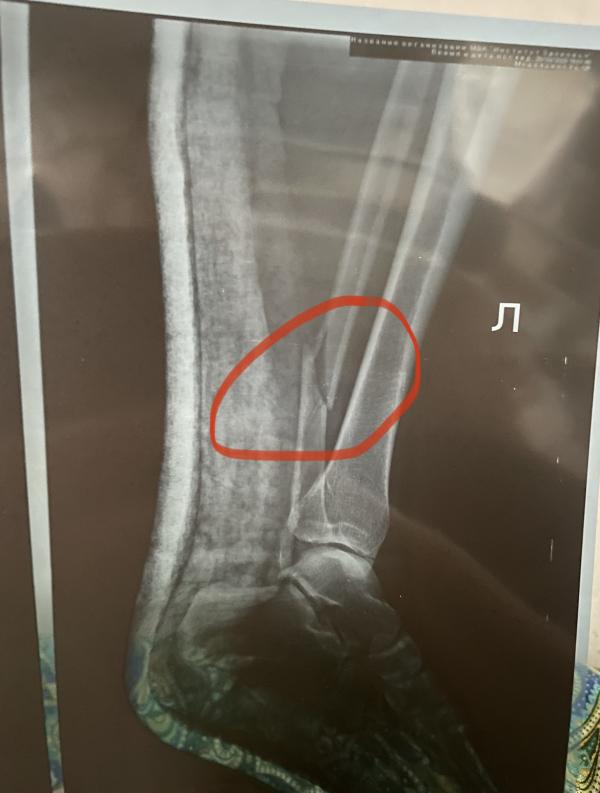

Ой, можно я вас поддержу своей историей? Я сломала ногу 24 ноября, трехлодыжечный перелом. Из-за сильного смещения неделю на вытяжке пролежала, потом была операция под проводниковой анестезией. Еще делают седативный укол, чтобы спать и не слышать всех этих сверлений) после операции гипс не накладывали, что я считаю плюсом, потому что ногу нужно сразу начинать разрабатывать. Полтора месяца на костылях проскакала и затем была еще мини-операция, выкручивали винт, который удерживал две кости вместе из-за разрыва связок. Ну а сейчас 4 мес после операции, хожу безо всяких приспособ, практически не хромаю. Ноге конечно далеко до здоровой, тут главное не забивать на лфк, разработку. В общем не переживайте, починят вам ногу и все заживет) =)